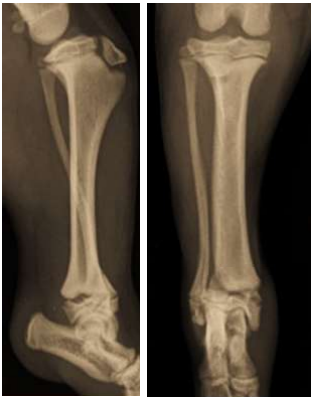

As radiografias abaixo pertencem a um Fox Terrier de 17 semanas de idade e evidenciam uma fratura

distal da tíbia. Trata-se de uma fratura fechada, que se estende por três quartos da linha fisária tibial,

prolongando-se até a metáfise lateral da tíbia:

A fratura não apresenta comunicação com a superfície articular. Com base nessa descrição, qual das seguintes opções melhor classifica essa fratura?